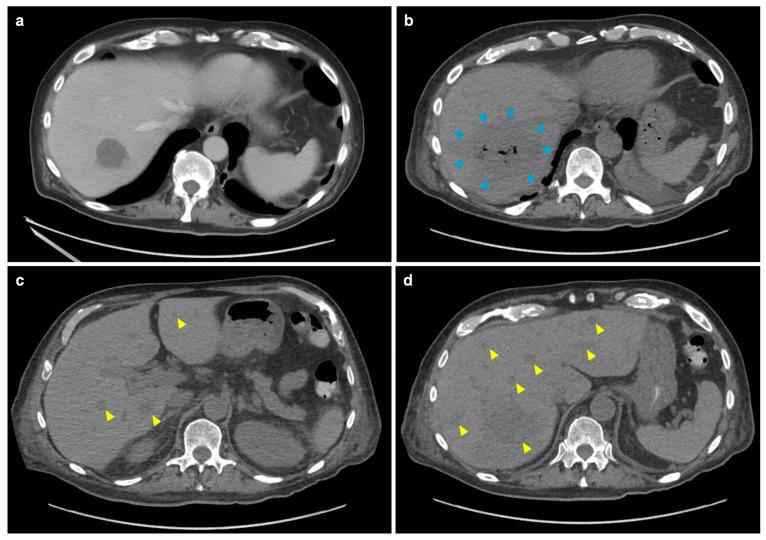

Hepatic mucormycosis is a rare but often fatal opportunistic fungal infection, primarily affecting immunocompromised patients. Herein, we report such a case from MD Anderson Cancer Center (Houston, TX, USA) and systematically review published cases in patients ≥ 19 years of age to better characterize clinical presentation, diagnostic challenges, and treatment outcomes of hepatic mucormycosis. Among the 40 identified cases (including ours), hematologic malignancies (55%) and solid organ transplantation (30%) were the most common underlying conditions. Fever (70%) and abdominal pain (63%) were the predominant symptoms. Imaging revealed multiple hepatic lesions in 72% of cases. Diagnosis was primarily based on histopathology (73%), whereas culture positivity was low (36%), underscoring the difficulty of pathogen isolation. Mucorales-active antifungal therapy was often delayed but eventually used in 85% of cases (all amphotericin B +/- Mucorales-active triazoles), while 45% underwent additional surgical intervention. Despite treatment, 1-year all-cause mortality remained high at 46%, with a trend towards lower mortality for those who underwent surgery compared to non-surgical management (35% vs. 55%, = 0.334). These findings highlight the aggressive nature of hepatic mucormycosis and the importance of early recognition as well as the need for non-culture-based diagnostics and multimodal treatment approaches. Improved awareness and further research into optimized management strategies are crucial to improve the outcomes of this challenging infection.

肝毛霉病是一种罕见但往往致命的机会性真菌感染,主要影响免疫功能低下的患者。在此,我们报告了美国德克萨斯州休斯顿市MD安德森癌症中心的这样一个病例,并系统回顾了19岁及以上患者中已发表的病例,以更好地描述肝毛霉病的临床表现、诊断挑战和治疗结果。在40例确诊病例(包括我们的病例)中,血液系统恶性肿瘤(55%)和实体器官移植(30%)是最常见的基础疾病。发热(70%)和腹痛(63%)是主要症状。72%的病例影像学检查显示肝脏有多个病变。诊断主要基于组织病理学(73%),而培养阳性率较低(36%),这凸显了病原体分离的困难。对毛霉目有效的抗真菌治疗常常延迟,但最终85%的病例使用了该治疗(均为两性霉素B±对毛霉目有效的三唑类药物),同时45%的病例接受了额外的手术干预。尽管进行了治疗,但1年全因死亡率仍高达46%,与非手术治疗相比,接受手术治疗的患者死亡率有降低趋势(35%对55%,P = 0.334)。这些发现突出了肝毛霉病的侵袭性、早期识别的重要性以及对非培养诊断和多模式治疗方法的需求。提高认识并进一步研究优化管理策略对于改善这种具有挑战性的感染的治疗结果至关重要。